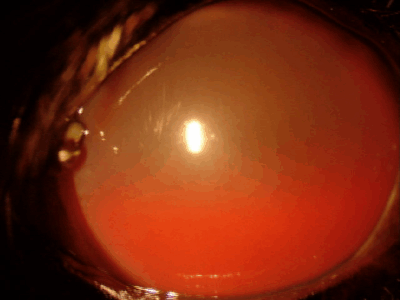

眼内出血

目の中で出血が起こり、黒目全体が赤く見えます。虹彩、毛様体、網膜、脈絡膜などの異常により起こることがあります。原因としてはぶどう膜炎、慢性緑内障、眼内腫瘍、網膜剥離などがあり、また全身性の高血圧で起こることもあります。失明につながる病気の可能性が高く、注意が必要です。